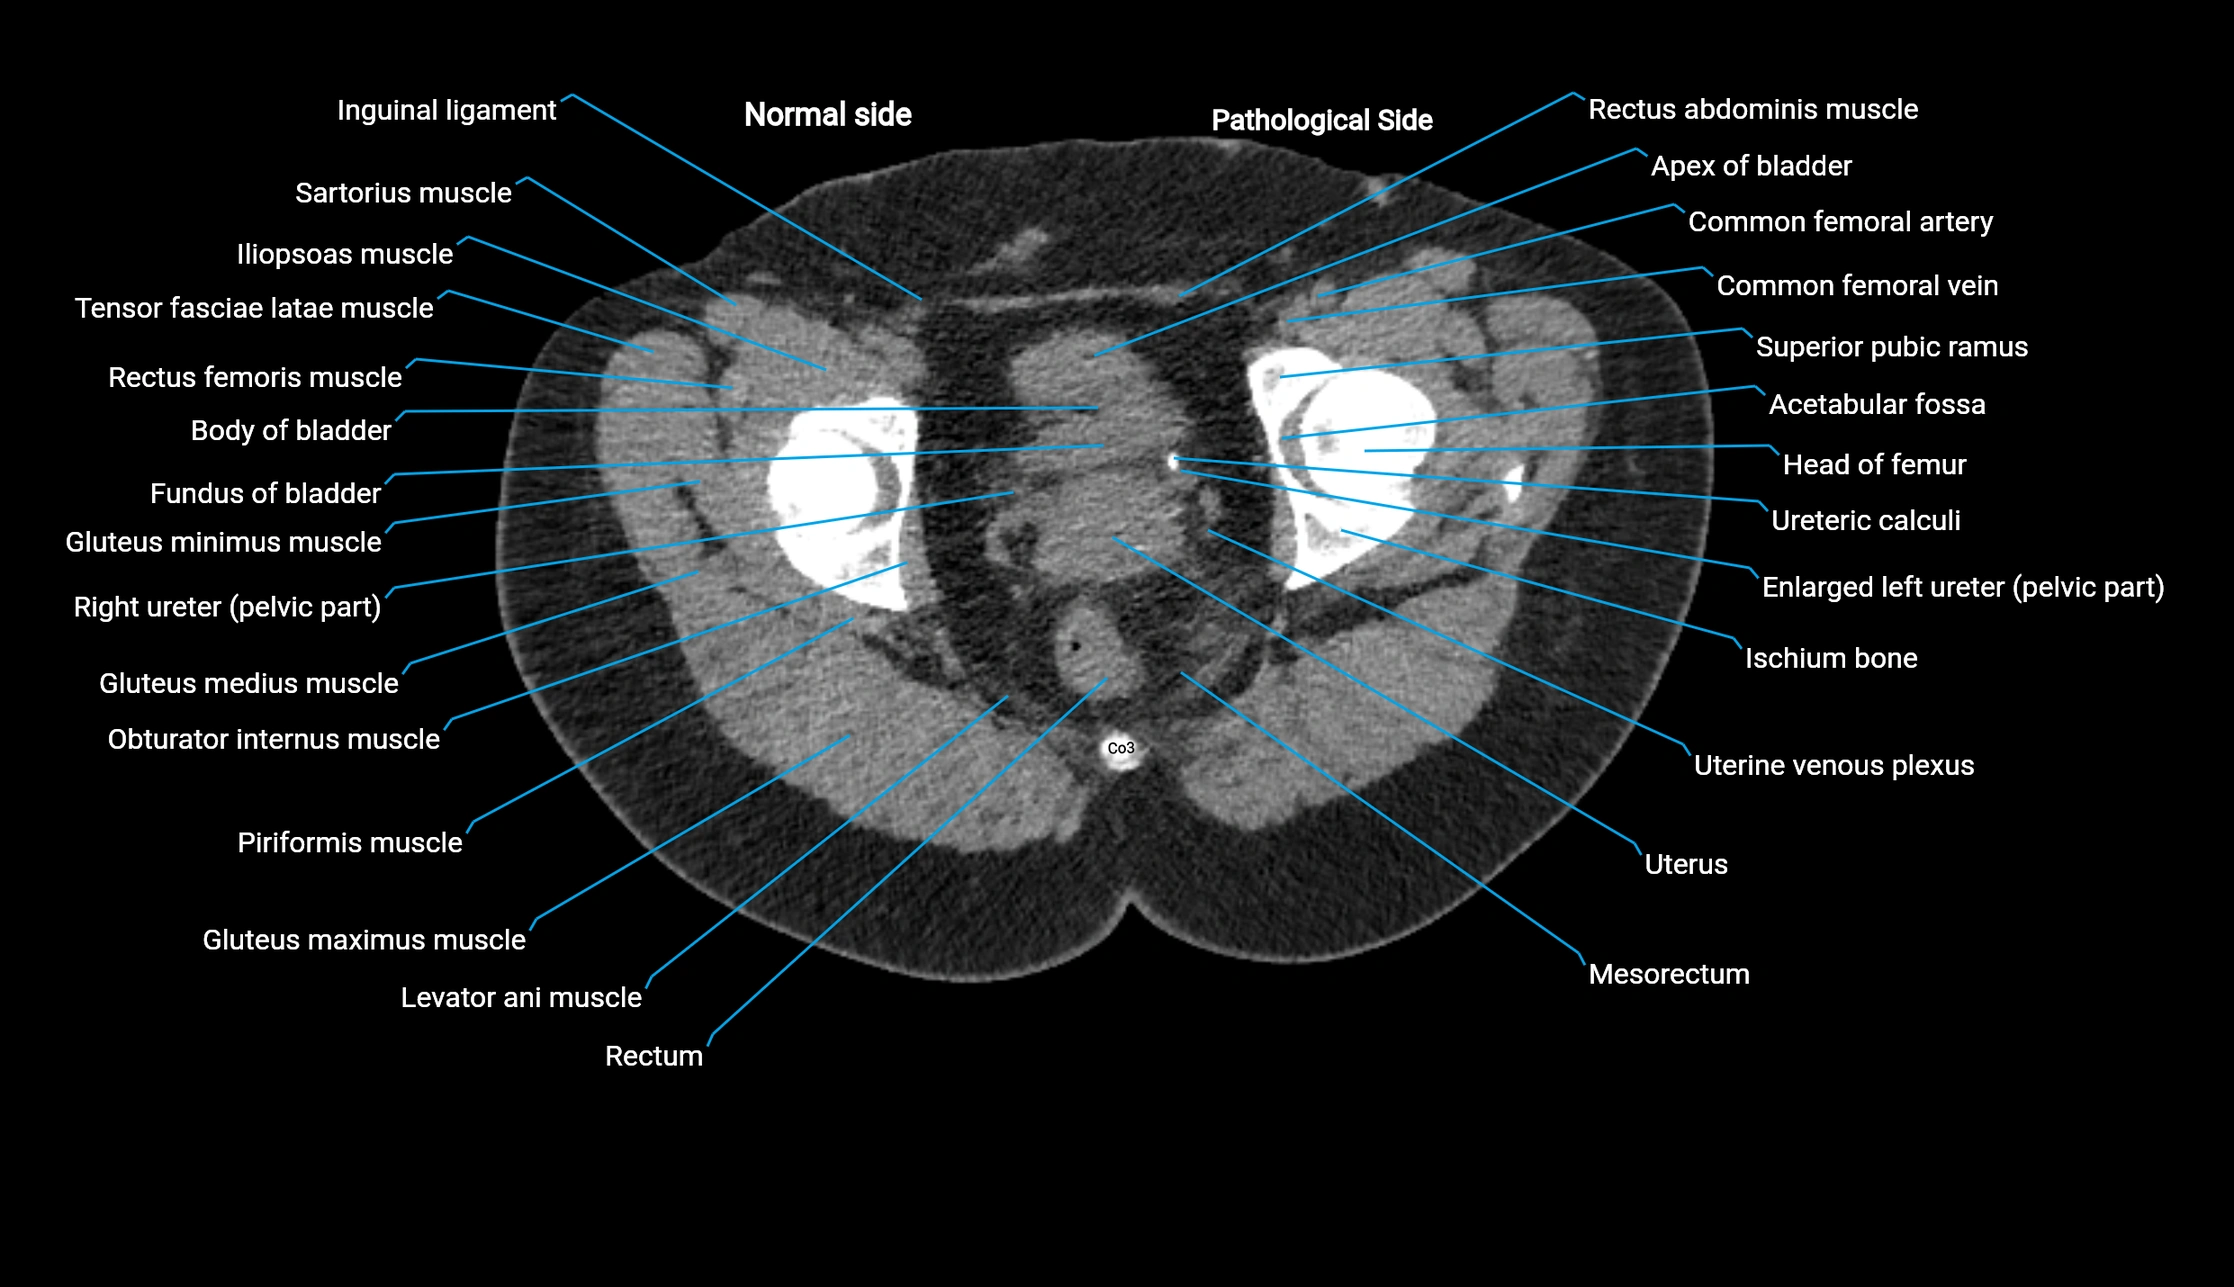

CT image

image